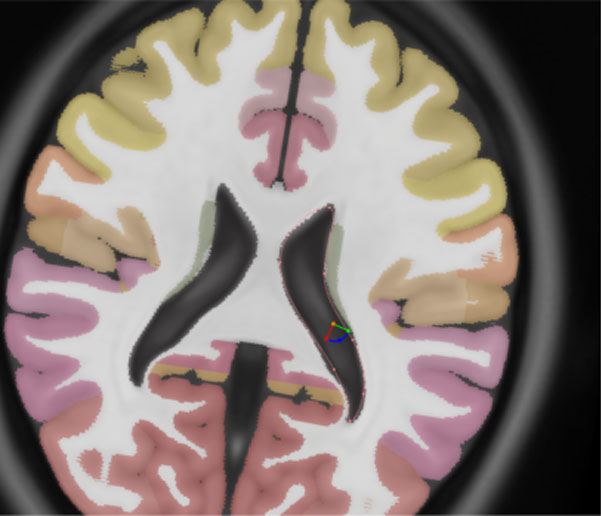

- Allen Institute for Brain Science